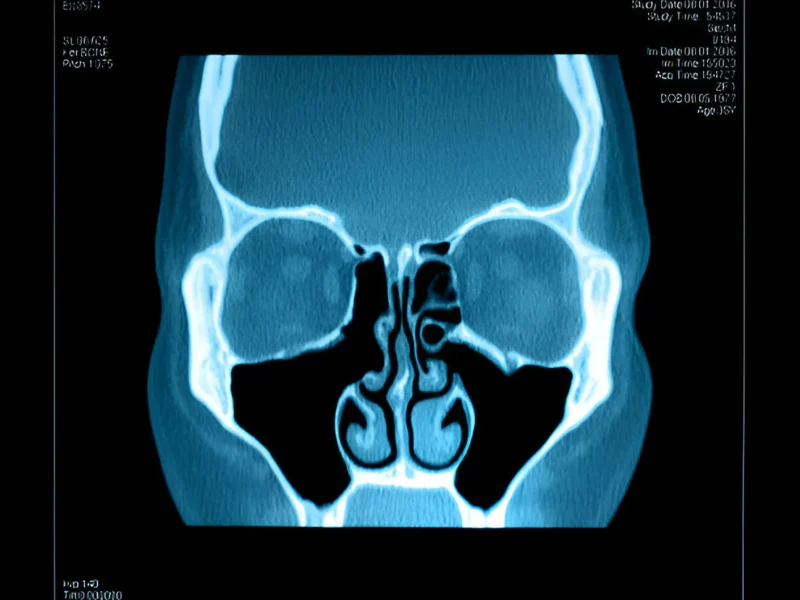

Millions of individuals worldwide suffer from the common medical disease known as sinusitis. When the sinus cavities swell and become inflamed, it can lead to symptoms such as nasal congestion, facial pain, headaches, and difficulty breathing. While sinusitis can be uncomfortable and disruptive, timely treatment can provide relief and prevent long-term complications. If you are looking for reliable Sinusitis Treatment in Hyderabad, Amrita ENT Hospital offers expert care with advanced techniques to manage and treat the condition effectively.

• Image-Guided Surgery: Advanced imaging techniques help surgeons precisely target affected areas with minimal damage to surrounding tissues.